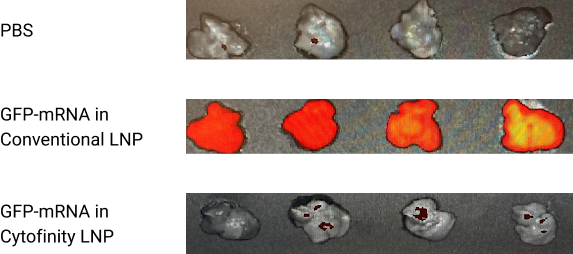

As shown in the figure below, 48 hours after systemically injecting Cytofinity LNP and traditional LNP loaded with a GFP-mRNA, the Cytofinity group exhibited much lower GFP expression in the liver than the traditional LNP group. This indicates that Cytofinity LNPs can detarget the liver and thus reduce LNP-mediated liver toxicity.

Ex vivo IVIS on Liver at 48-hr